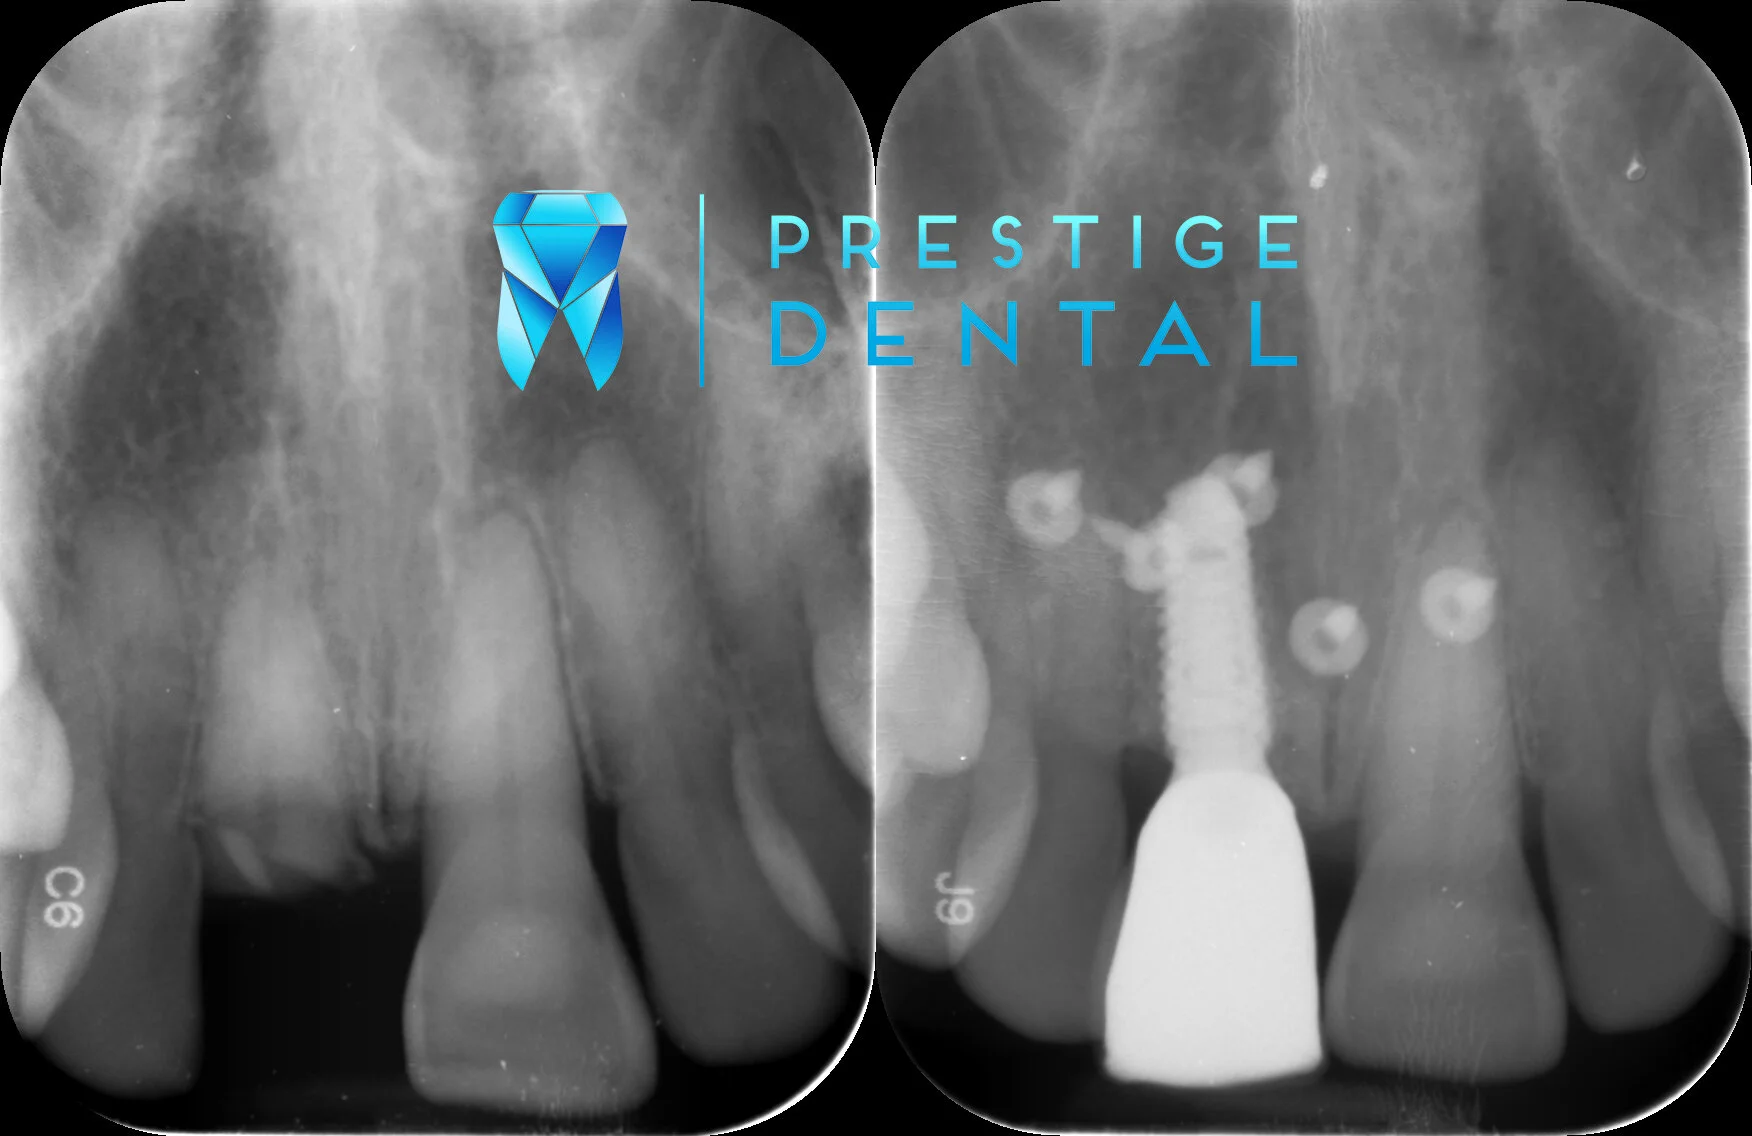

Prestige Dental Implant Sample.jpg

A dental implant is a replacement tooth held in place by a titanium or ceramic fixture in the jaw. Dental implants have excellent longevity and can achieve life-like appearances. These are preferred method of replacing missing teeth because they are comfortable, functional, aesthetic, easily cleansible and can last a lifetime with proper care.

Placing an implant is a complex process and the over condition of the mouth must be taken into consideration. A full examination including a thorough health questionnaire is mandatory for any implant planning process. Once it is determined that you are a good candidate for an implant surgery, you will be referred to a specialist oral surgeon, who may take further records to plan the surgery. This is extremely important as poorly placed implants can cause major problems and very high costs to fix.

The implant can be placed either immediately at the time the existing tooth is removed, or can be placed after depending on the situation. In some cases you may require bone grafting to allow more support for the implant. Once the implant is placed, there is usually a healing period up to 6 months. Once the implant is well integrated into your bone, an abutment (the ‘tooth’ portion) will be placed to replace the missing tooth.